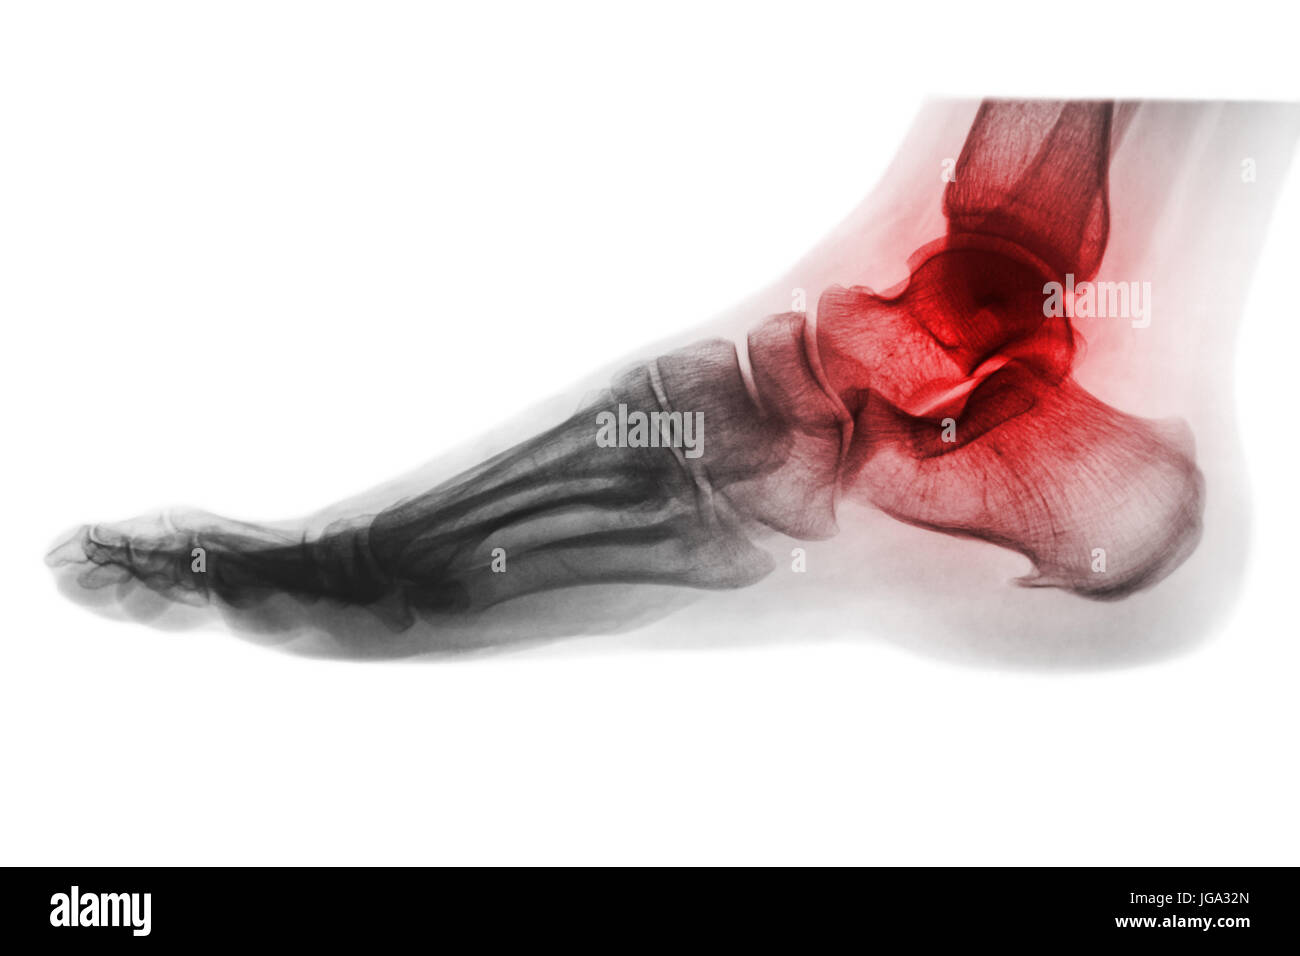

Arthritis of ankle . Xray of foot . Lateral view . Invert color style Severe Arthritis In Ankle Xray The average age of the patient affected by ankle oa is around 50 years, being therefore active patients and in working age. Ankle arthritis is a common degenerative joint disease of the tibiotalar joint that presents with pain, stiffness, and deformity of the ankle. Most commonly caused by post. The most severe feature(s) of the osteoarthritis, such as joint space. Severe Arthritis In Ankle Xray.

Arthritis and injury at ankle film xray of child 's foot ( side view Severe Arthritis In Ankle Xray Narrowing of the joint space between bones (a sign of cartilage loss), changes in the bone (such as fractures) the formation of bone spurs; The average age of the patient affected by ankle oa is around 50 years, being therefore active patients and in working age. Any varus/valgus deformity, and if such, the degree. Most commonly caused by post. The. Severe Arthritis In Ankle Xray.